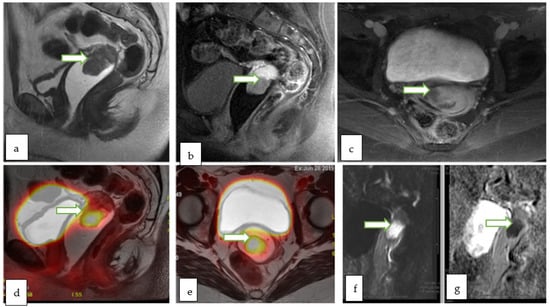

- PET-MRI allows a one-stop assessment of gynecological malignancies, combining the functional and quantitative metabolic data of PET with the high-resolution anatomic and functional imaging properties of MRI. Although it shows promising diagnostic performance, limited data in the literature exists regarding the justification of its high cost compared to separately acquired PET-CT and MRI.